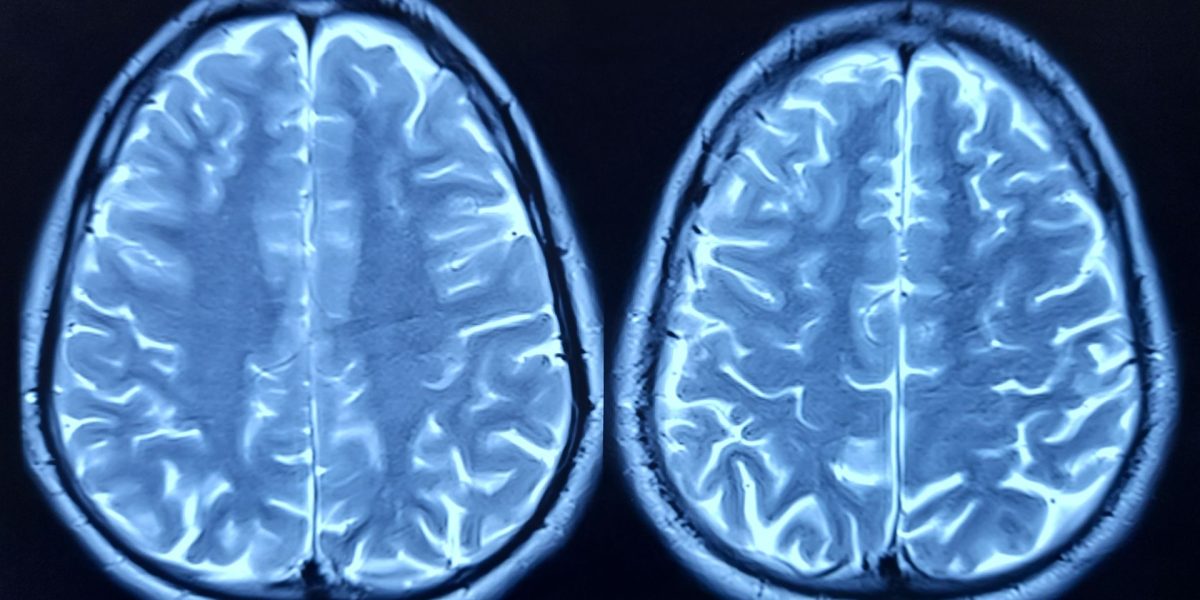

Îmbătrânirea creierului este un proces complex, cu efecte severe asupra funcțiilor cognitive, în special asupra memoriei. Echipa de cercetători de la Universitatea din CALIFORNIA, SAN FRANCISCO (UCSF) a investigat modificările moleculare care apar în hipocamp, regiunea creierului crucială pentru învățare și memorare. Studiul a urmărit evoluția genelor și a proteinelor din hipocampul șoarecilor, observând diferențe constante între animalele tinere și cele mai în vârstă. Așa au descoperit FTL1, o proteină ale cărei niveluri crescute par să fie direct legate de declinul cognitiv.

Șoarecii mai bătrâni, cu niveluri ridicate de FTL1, au prezentat mai puține conexiuni între neuroni. În plus, au avut rezultate mai slabe la testele cognitive. Experimentele au arătat că, atunci când cercetătorii au crescut nivelul de FTL1 la șoarecii tineri, creierele acestora au început să arate semne de îmbătrânire, iar comportamentul lor a reflectat această schimbare.

Experimentele de laborator au oferit informații suplimentare. Celulele nervoase modificate genetic pentru a produce cantități mari de FTL1 au dezvoltat structuri simplificate, cu extensii scurte, în loc de rețele complexe specifice celulelor sănătoase. Rezultatul cel mai surprinzător a apărut atunci când cercetătorii au redus nivelul de FTL1 la șoarecii bătrâni. Conexiunile dintre celulele cerebrale au crescut, iar performanța la testele de memorie s-a îmbunătățit. „Este cu adevărat o inversare a deficiențelor”, a declarat Dr. Saul VILLEDA, director adjunct al Institutului de Cercetare a Îmbătrânirii BAKAR din cadrul UCSF. “Este mult mai mult decât o simplă întârziere sau prevenire a simptomelor.”

Studiul a arătat că FTL1 afectează modul în care celulele cerebrale utilizează energia. La șoarecii bătrâni, nivelurile ridicate ale proteinei au încetinit metabolismul celular în hipocamp. Când cercetătorii au tratat aceste celule cu un compus care stimulează metabolismul, efectele negative au fost prevenite. Aceste descoperiri ar putea deschide calea către tratamente care să vizeze proteina FTL1 și să contracareze efectele acesteia în creier.